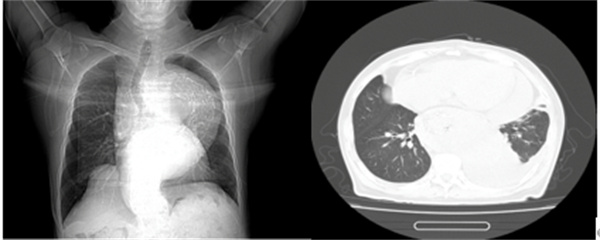

图表2 一位尚未透析的终末期肾脏病患者

也就是我们常说的“围透析期”,通常发生在刚开始透析,或者透析不充分的患者身上透析不充分,我们图中第二例患者就是一位未及时开始透析的终末期透析患者。如果透析次数不够、时间不足,毒素清除得不够理想,依然会持续刺激心包。